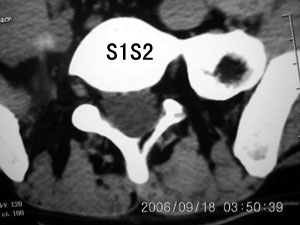

以下是引用守望可可西里在2006-9-18 21:29:00的发言:[br][br] 马尾肿瘤,密度较低,大部分似乎呈囊性变(看着很费眼),考虑室管膜瘤,建议mri。

以下是引用dyg在2006-9-18 22:27:00的发言:[br]正常脊髓.[br]分析:人的脊髓从枕大孔开始至腰1.2椎体为止,有2个生理膨大,分为颈膨大和腰膨大;该病人脊髓须然从腰段开始直至马尾似乎膨大,胆是与上段脊髓密度没有多大变化,所以我认为是正常膨大之延续;当然最好做ct增强或mri检查,排除肿瘤.

以下是引用飞虎在2006-9-18 20:18:00的发言:[br]部分椎管内密度不均且无ct值 故mri检查